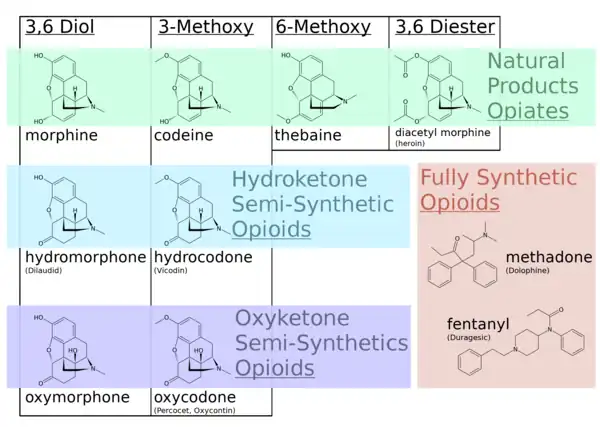

In the 19th century, two major scientific advances were made that had far-reaching effects. Around 1804, German pharmacist Friedrich Sertürner isolated morphine from opium. He described its crystallization, structure, and pharmacological properties in a well-received paper in 1817.[211][213][208][214] Morphine was the first alkaloid to be isolated from any medicinal plant, the beginning of modern scientific drug discovery.[211][215]

Semisynthetic and synthetic opioids

Several semi-synthetic opioids were developed in Germany in the 1910s. The first, oxymorphone, was synthesized from thebaine, an opioid alkaloid in opium poppies, in 1914.[228] Next, Martin Freund and Edmund Speyer developed oxycodone, also from thebaine, at the University of Frankfurt in 1916.[229] In 1920, hydrocodone was prepared by Carl Mannich and Helene Löwenheim, deriving it from codeine. In 1924, hydromorphone was synthesized by adding hydrogen to morphine. Etorphine was synthesized in 1960, from the oripavine in opium poppy straw. Buprenorphine was discovered in 1972.[228]

The first fully synthetic opioid was meperidine (later demerol), found serendipitously by German chemist Otto Eisleb (or Eislib) at IG Farben in 1932.[228] Meperidine was the first opiate to have a structure unrelated to morphine, but with opiate-like properties.[199] Its analgesic effects were discovered by Otto Schaumann in 1939.[228] Gustav Ehrhart and Max Bockmühl, also at IG Farben, built on the work of Eisleb and Schaumann. They developed "Hoechst 10820" (later methadone) around 1937.[230] In 1959 the Belgian physician Paul Janssen developed fentanyl, a synthetic drug with 30 to 50 times the potency of heroin.[211][231] Nearly 150 synthetic opioids are now known.[228]

There are a number of broad classes of opioids:[260]

- Natural opiates: alkaloids contained in the resin of the opium poppy, primarily morphine, codeine, and thebaine, but not papaverine and noscapine which have a different mechanism of action

- Esters of morphine opiates: slightly chemically altered but more natural than the semi-synthetics, as most are morphine prodrugs, diacetylmorphine (morphine diacetate; heroin), nicomorphine (morphine dinicotinate), dipropanoylmorphine (morphine dipropionate), desomorphine, acetylpropionylmorphine, dibenzoylmorphine, diacetyldihydromorphine;[261][262]

- Semi-synthetic opioids: created from either the natural opiates or morphine esters, such as hydromorphone, hydrocodone, oxycodone, oxymorphone, ethylmorphine and buprenorphine;

- Fully synthetic opioids: such as fentanyl, pethidine, levorphanol, methadone, tramadol, tapentadol, and dextropropoxyphene;